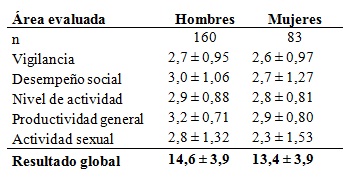

El puntaje global del cuestionario de resultados funcionales del sueño (FOSQ) en 243 pacientes (160 hombres y 83 mujeres) estuvo muy disminuido: 14,56 ± 3,9 para los hombres y 13,40 ± 3,9 para las mujeres, indicando una considerable repercusión diurna del trastorno del sueño. La puntuación tiene un valor mínimo de 0 (máximo impacto funcional) y un valor máximo de 24 (ningún impacto). (Tabla 5).

Tabla 5: Cuestionario de resultados funcionales del sueño

Tabla 5. Puntajes obtenidos mediante el cuestionario FOSQ (n=243)